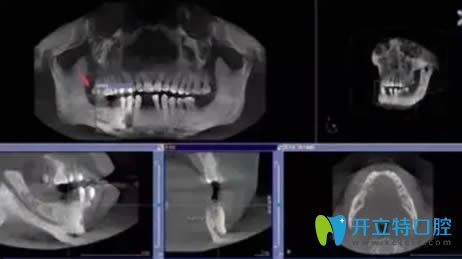

廈門麥芽口腔精準(zhǔn)種植牙直播:親眼見證數(shù)字化種植牙全過程

人工種植牙種植牙的過程廈門口腔發(fā)布時(shí)間: 2025-04-16

廈門麥芽口腔醫(yī)院3D數(shù)字化精準(zhǔn)種植牙直播公益大講堂開始啦!親眼見證種植牙全過程,種牙整個(gè)流程就是這么輕松~~別再忍受缺牙的痛苦嘍!